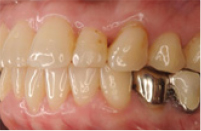

治療後